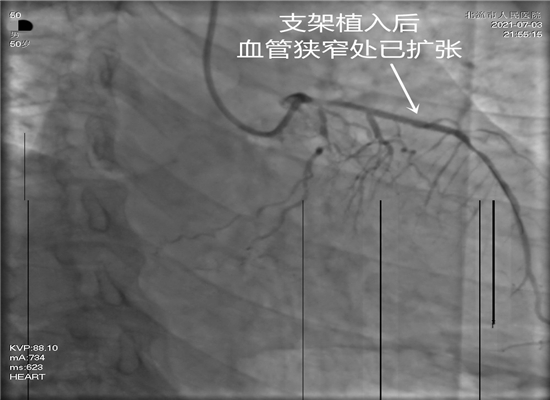

时间就是生命,这是一场与死神生死竞速的硬仗。21时15分,病人进入导管室,在赵子粼博士的主持下,张轩副主任亲自操刀,介入团队密切配合,快速穿刺桡动脉、置管、造影,升压,开通闭塞血管,植入支架。经过约50分钟的全力救治,成功挽救了患者的生命。目前,术后患者症状明显改善,恢复较好。

支架植入后血管狭窄处已扩张